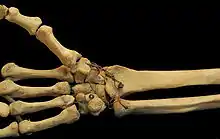

Articulación carpometacarpiana

Las articulaciones carpometacarpianas (CMC) son cinco articulaciones de la muñeca que articulan la fila distal de los huesos del carpo y las bases proximales de los cinco huesos metacarpianos.